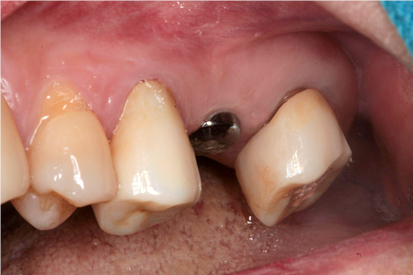

Tooth Site: #26

Maxillary sinusitis secondary to implant placement at #26 performed at an outside clinic.

A panoramic radiograph revealed radiopacity within the left maxillary sinus. Clinical findings were consistent with implant-associated sinusitis at the #26 site.

Diagnosis: Implant-associated maxillary sinusitis